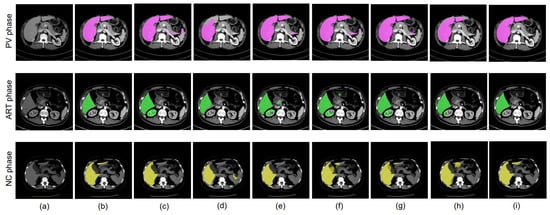

4.8.3. Different Datacenter and Different Phase